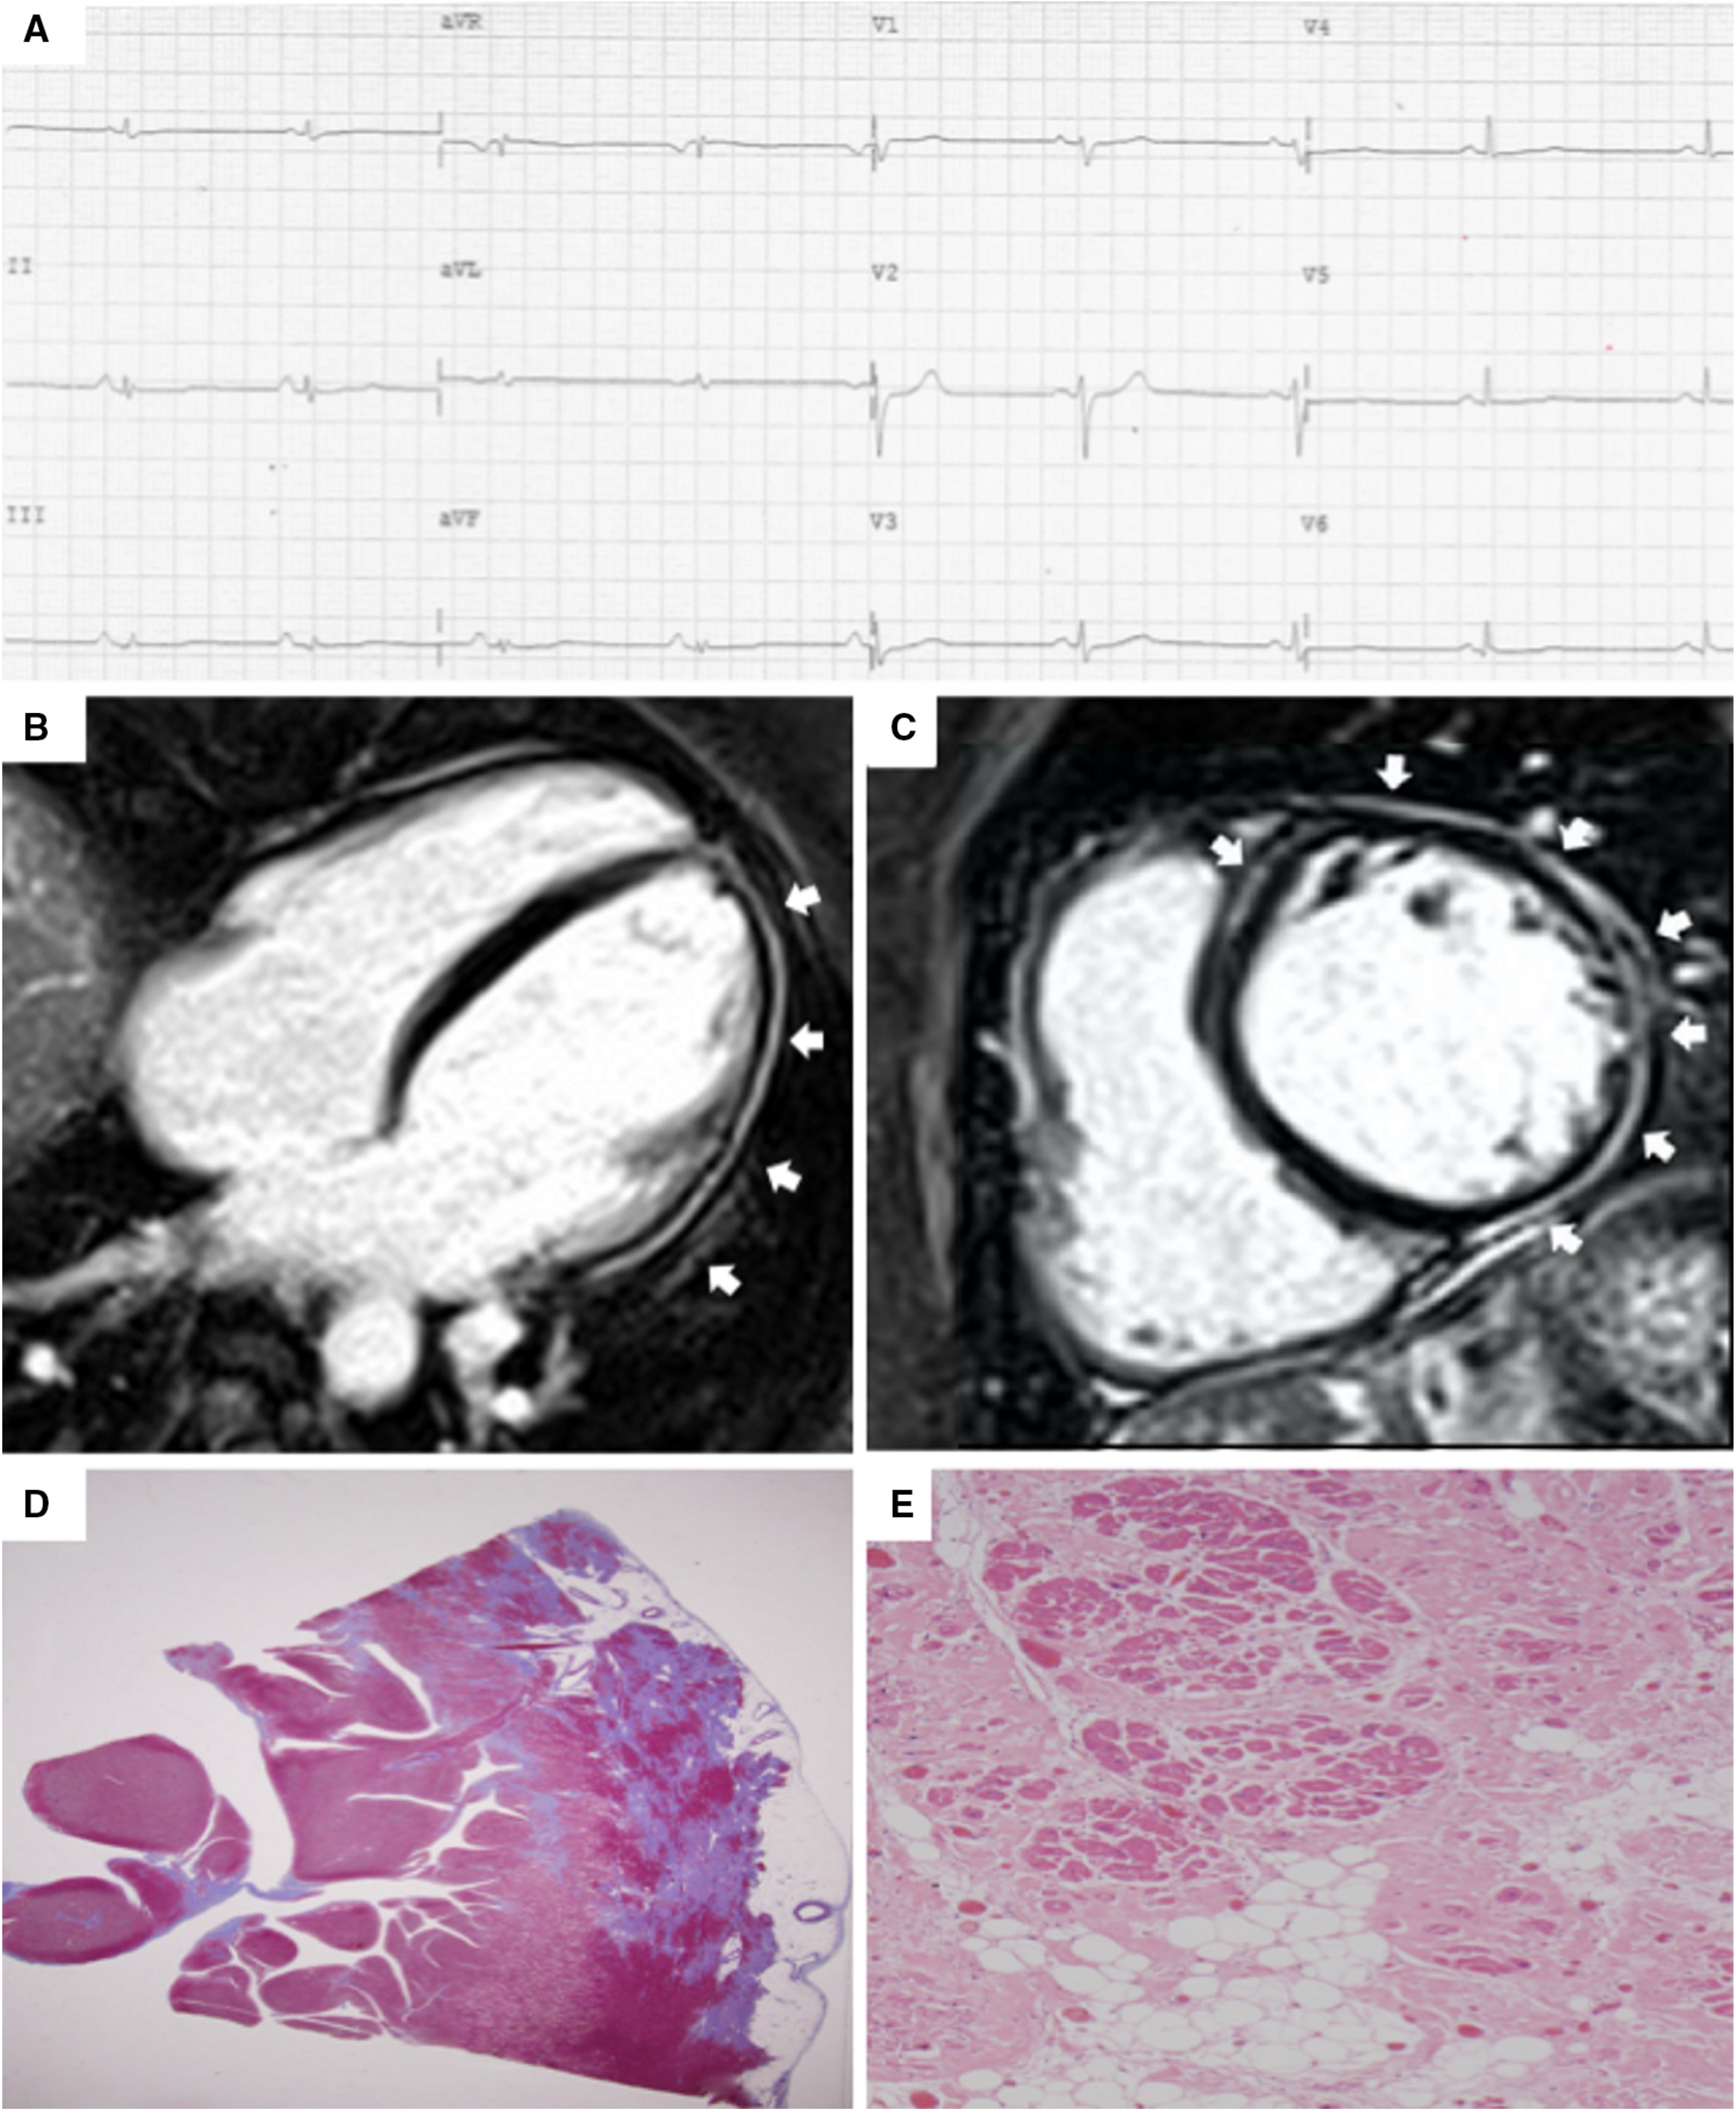

In the LV, the presence of a stria of LGE with a non-ischemic distribution (subepicardial and/or midmyocardial, most affecting the inferolateral region) in at least 1 LV Bull’s Eye segment, confirmed in 2 orthogonal views (excluding junctional LGE, that is considered non pathologic) is a major criterion. Moreover, the circumferential involvement of septum and LV free wall in short axis view is called “ring-like” pattern, and it is considered as highly specific for ALVC [32]. Nonetheless, at present there is no gold standard for differentiating non-ischemic LGE secondary to ACM or to other diseases such as myocarditis: for this reason, in the absence of concomitant RV involvement, the diagnosis of left-dominant ACM in a proband requires positive genetic testing (Fig. 1). Fatty tissue infiltration is often observed on dedicated CMR sequences, but it is not considered a diagnostic criterion in isolation because of its low specificity.

In the early stages of LV involvement, the typical non-ischemic distribution of fibro-fatty replacement sparing the subendocardial layer can explain the absence of wall motion abnormalities, dilatation, or dysfunction of the LV. Thereby, the absence of LV functional abnormalities on echo, cine-CMR or angiography cannot rule out LV involvement, and CE-CMR characterization plays a key role in detection of left-sided ACM [14, 16, 33, 34, 35, 36] (Fig. 4, Ref. [14]).

Fig. 4.

Fig. 4.Clinical and histopathological features of ALVC. Basal ECG and CMR findings in a patient who underwent cardiac transplantation because of ALVC related to a DSP gene mutation. Basal ECG revealed low QRS voltages in limb leads and flattened T-waves in infero-lateral leads (A). Post-contrast sequences on CMR (four-chamber view, B, and short-axis view, C) revealed subepicardial LGE involving the anterior septum and the whole LV free wall (“ring like” pattern) from basal to apical regions. Histology in LV inferolateral region demonstrated fibrofatty myocardial replacement in the subepicardial layer (D); a magnification of residual myocytes embedded within fibrous and fatty tissue (hematoxylin and eosin stain) (E). The diagnosis was “definite ALVC”. ALVC, arrhythmogenic left ventricular cardiomyopathy; CMR, cardiac magnetic resonance; DSP, desmoplakin gene; LGE, late gadolinium enhancement; LV, left ventricle. Adapted from Cipriani et al. [14].